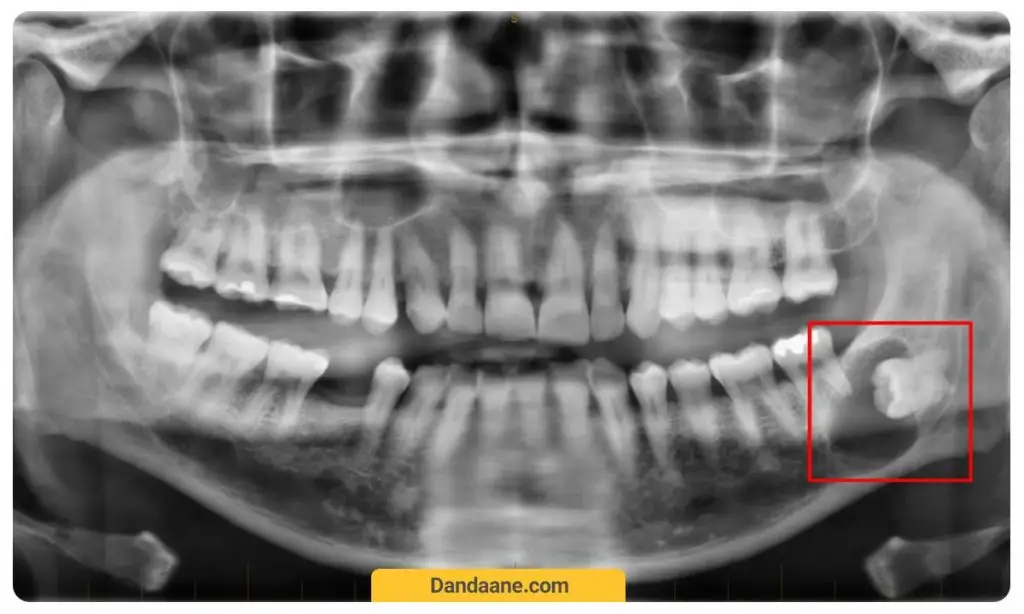

او پی جی یا opg در اصل مخفف عبارت Orthopantomagram است یا ارتوپانتوگرام است که به آن پانورکس (Panorex) یا عکس پانورامیک دندان نیز گفته می شود. این یکی از رایج ترین رادیوگرافی های مربوط به دهان و دندان است که کاربردهای بسیار زیادی در دندانپزشکی دارد.

او پی جی در واقع نوعی عکس برداری پانورامیک (عکس گسترده از جهات مختلف) است که توسط اشعه ایکس از دندان های فک بالا و پایین گرفته شده و یک نمای دو بعدی مسطح نیم دایره ای از زیر یک گوش تا زیر گوش دیگر را به دندانپزشک نشان می دهد. این عکس شامل هر دو فک بالا و پایین به صورت کامل و تمام دندان های حاضر در آن ها است.

- تشخیص دندان عقل پنهان و برنامه ریزی جهت درمان اختصاصی آن